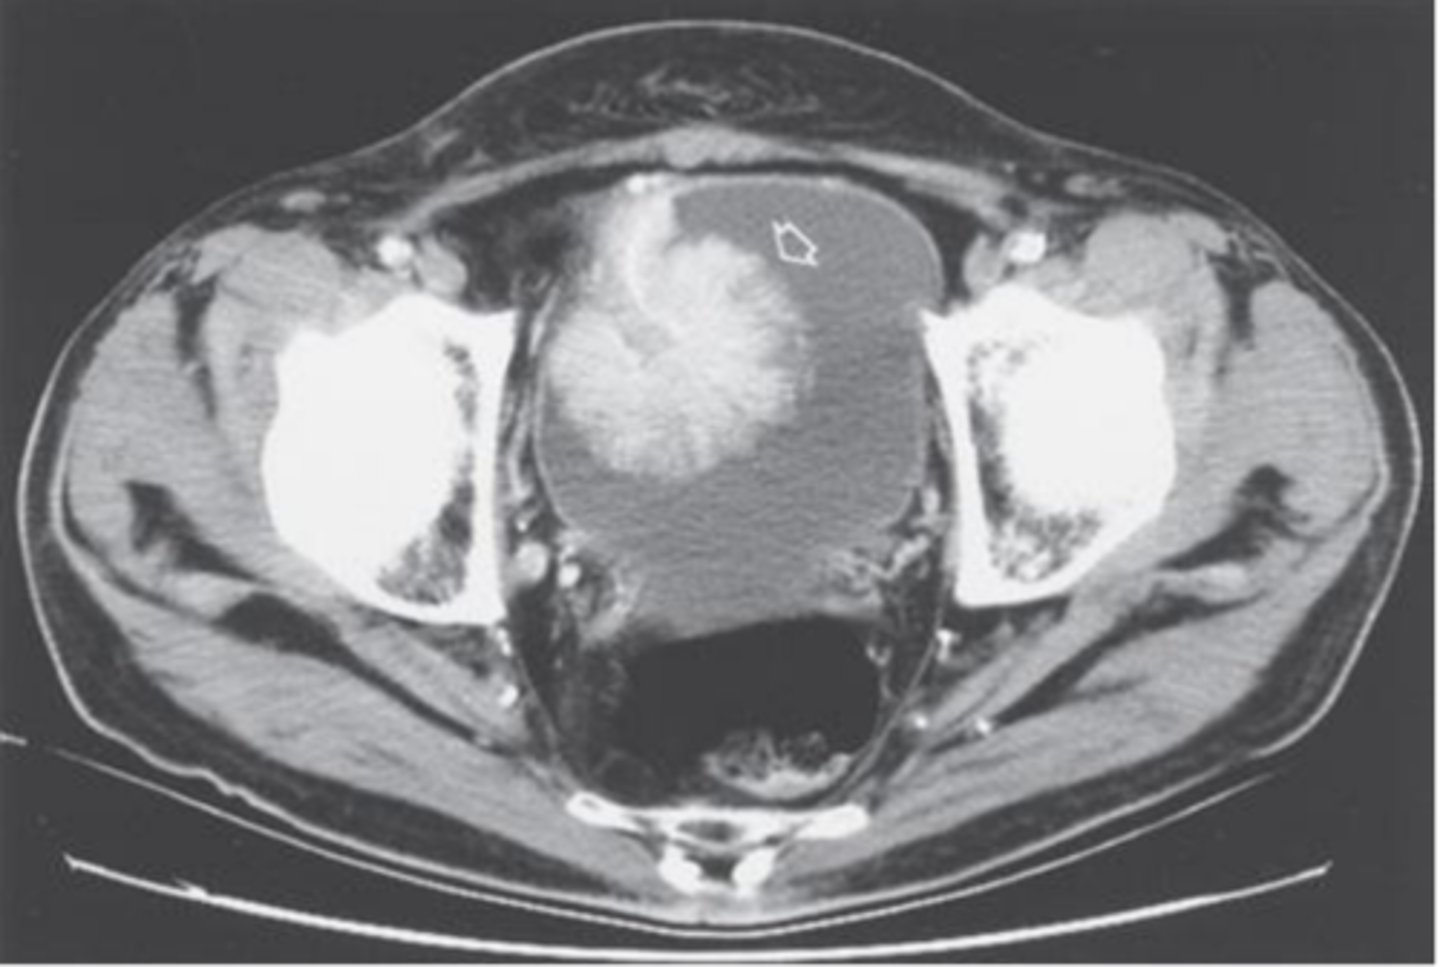

How is bladder cancer diagnosed? What is the gold-standard?

UA (looking for hematuria), urine cytology (not sensitive, very specific tho), CT abdomen & pelvis w/ & w/o contrast plus delayed imaging (most sensitive), IVP or retrograde pyelogram (safe for patients w/ IV contrast allergies), cystoscopy w/ biopsy is definitive (gold-standard)